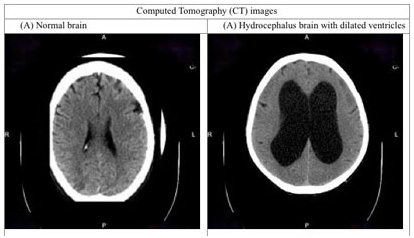

Normal pressure hydrocephalus (NPH) is a brain disorder whereby cerebrospinal fluid (CSF) – a clear, colorless body fluid surrounding your brain and spinal cord, accumulates in your brain’s ventricles, causing them to become enlarged. The brain’s ventricles are cavities in your brain filled with CSF. As these ventricles enlarge, they press and thus damage nearby brain tissue, resulting in problems with thinking, reasoning, memory and control over certain parts of your body.

In addition, your doctor will make use of neuroimaging, such as CT and MRI scans to detect abnormal enlargement of the brain’s ventricles. This will also aid in differentiating NPH from other diseases which may have similar symptoms as NPH, such as Alzheimer’s.